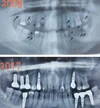

Fotoğraflar